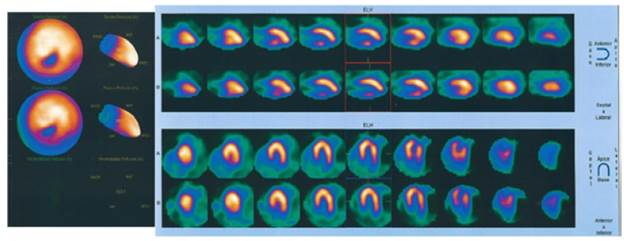

This paper reports the case of 52-year-old male patient, from Bogotá D.C., without ethnicity, and architect for profession. He presented with a history of dyslipidemia, and consulted due to a 6-month history of episodes of sharp retrosternal chest pain that radiated to the back and neck, lasting less than 5 minutes, associated with moderate efforts and attenuation at rest. He also showed progressive deterioration of his functional class. Physical examination was normal and electrocardiogram showed sinus rhythm with a heart rate of 70 bpm, with changes compatible with necrosis in the lower and lateral sides. Transthoracic echocardiogram showed left ventricular ejection fraction of 58%, with segmental alterations in contractility due to severe hypokinesis in the apical lateral, apical infarction and concentric remodeling of the left ventricle with a non-mobile image of an 11x9mm calcium refringence suggestive of a small organized thrombus. For this reason, a myocardial perfusion with pharmacological stress (dipyridamole) was performed, which was negative for myocardial ischemia, with lower wall necrosis in the middle and distal segments. Figure 1 shows a severe perfusion defect in the middle and distal segments of the inferior wall, not reversible, and with mild hypokinesia; the estimated area of necrosis is 5-7% of the total myocardial mass.

Myocardial perfusion test with pharmacological stress.

Figure 1: Myocardial perfusion test with pharmacological stress.

Source: Document obtained during the study.